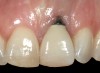

Fig 9. After 3 months of healing, the implant was uncovered. A crestal incision was made with a palatal bias and rolled to the labial side to increase the soft tissue to the facial aspect.

Figure 9

It was determined that additional augmentation was required to increase the soft-tissue volume, so a subepithelial connective tissue graft was acquired from the palate (Figure 8),23,24 placed, and allowed to mature for at least 3 months. Second-stage implant undercovering surgery with a palatal-biased incision was performed after tissue maturation to further thicken the labial soft tissues. In addition, a flat contoured healing abutment was placed to allow the soft tissues to mature without risk of recession, and the RBR replaced (Figure 9). After 4 to 6 weeks of healing, a flat contoured screw-retained provisional restoration was inserted (Figure 10) with the proper submergence profile to restoratively sculpt the soft tissues. An implant-level impression was made and the definitive cement-retained metal-ceramic restoration fabricated and inserted (Figure 11 through Figure 13). The final esthetic outcome to restore the proper length and proportion of the right lateral incisor to match that of the contralateral incisor was accomplished using the treatment steps outlined above, where the mucosal tissues were augmented after implant decoronation (Figure 14).